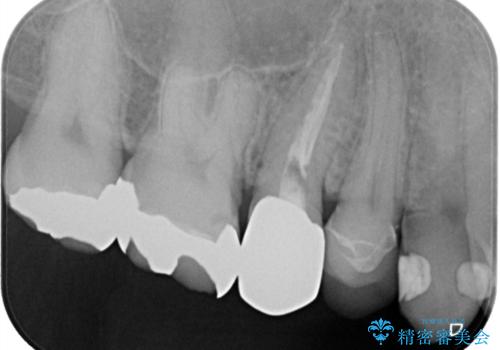

できるだけ歯質を残した1day治療 セラミックインレー

- 歯の詰め物が外れ、そのままにしていたのを治したいとのことで来院されました。残った歯質の量が少なく、できるだけ歯を残すために仮詰め期間の必要が無い1dayのセラミック治療を行いました。術後も経過良好です。処置においては虫歯も綺麗に除去しています。

1day治療は、仮詰めが不必要です。そのため、仮詰め期間中の残存歯質が欠けてしまうこともありません。また、口腔内の温度変化は食事等により50度近くあるといわれていますが、この間に仮詰めの材料は収縮・膨張を繰り返します。そこで生まれた隙間に汚れが入りこみ、これが接着力の低下やセット後の歯髄不快症状の原因となる可能性があります。1day治療にすることで、こうした因子を回避し歯の寿命を長くすることができます。